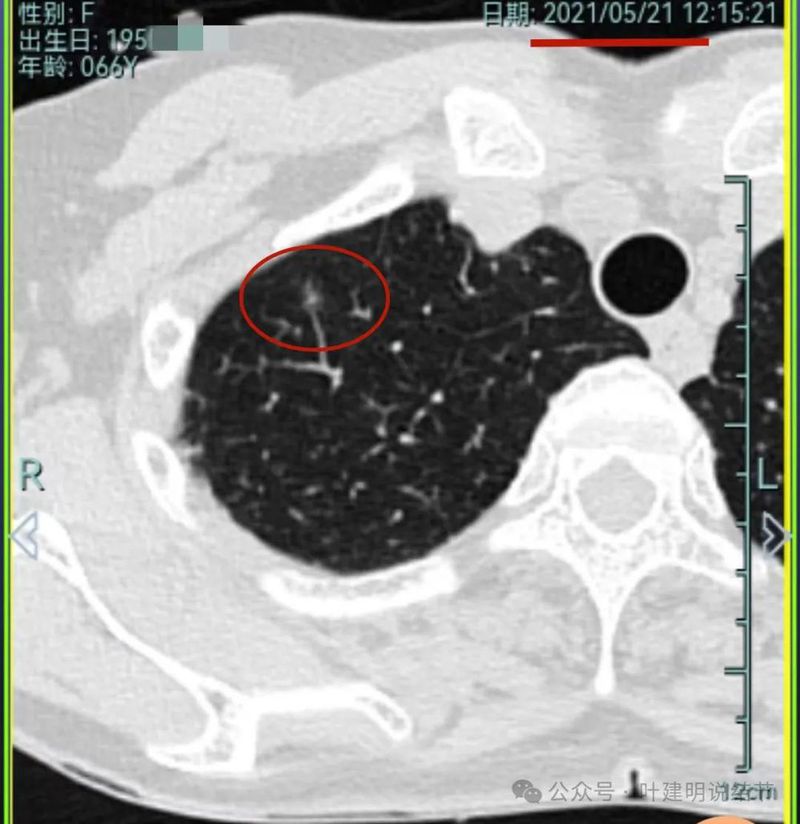

再看2021年随访的影像:

病灶1似乎中间高密度部分略有密度增高。

病灶6轮廓较前清楚,灶内有血管穿行,也有轻微胸膜牵拉。